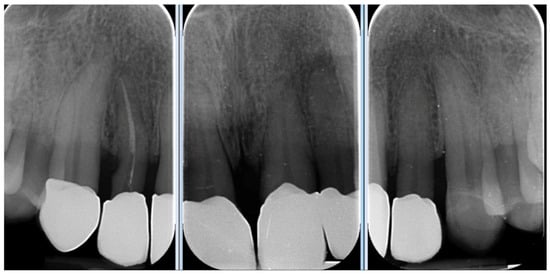

The patient was subsequently enrolled in a structured periodontal and prosthetic maintenance programme, with follow-up evaluations scheduled at four-month intervals to monitor periodontal health, occlusal stability, and the integrity of the prosthetic components (Figure 18, Figure 19 and Figure 20).

Figure 19. Intraoral image at four-year follow-up.

Figure 20. Four-year follow-up radiographic examination.

At the four-year follow-up, clinical evaluation demonstrated stable soft and hard tissues, with no biological or mechanical complications observed throughout the entire follow-up period.

At the four-year follow-up, the clinical situation remained stable and asymptomatic. Periodontal evaluation revealed probing depths within physiological limits, a low plaque index (7%), and minimal bleeding on probing (8%), all consistent with a healthy periodontal environment. Radiographic assessment confirmed the maintenance of alveolar bone levels without signs of resorption. The patient’s reduction in tobacco use and adherence to four-month maintenance therapy intervals likely played a pivotal role in sustaining these outcomes. The four-year follow-up also confirmed the clinical stability of the treatment, both occlusally and periodontally, with a significant improvement in clinical indices and complete patient satisfaction. Masticatory function remained effective, the deep bite was corrected, and the interincisal diastema was successfully closed, resulting in a harmonious and stable aesthetic outcome. The final decision to fabricate individual crowns was justified by the favourable tissue response and the occlusal stability achieved.